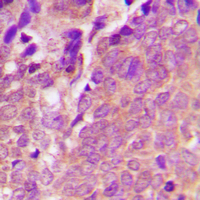

Immunohistochemical analysis of VASP (Phospho-S238) staining in human breast cancer formalin fixed paraffin embedded tissue section. The section was pre-treated using heat mediated antigen retrieval with sodium citrate buffer (pH 6.0). The section was then incubated with the antibody at room temperature and detected using an HRP conjugated compact polymer system. DAB was used as the chromogen. The section was then counterstained with haematoxylin and mounted with DPX.